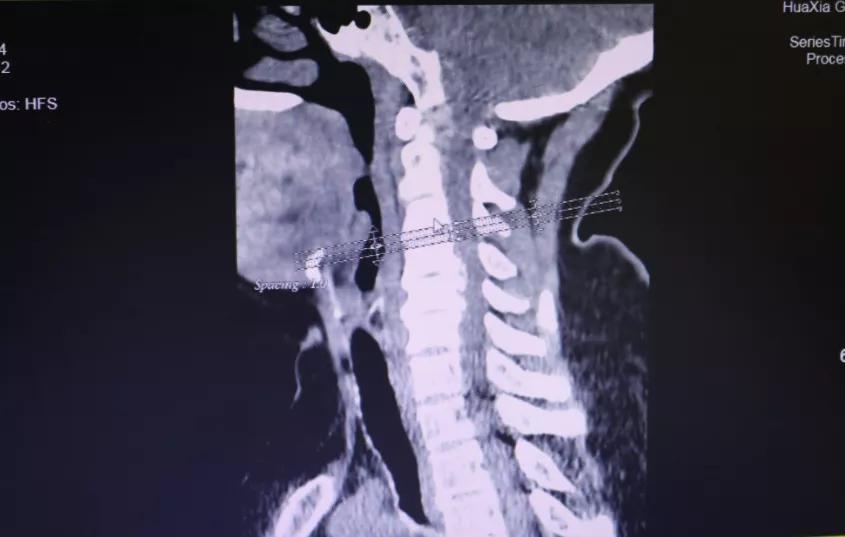

做了全面的检查后,胡阿姨被诊断为:颈椎病(脊髓型);颈椎间盘突出症 ;颈椎后纵带骨化症;肝功能不全 。患者诊断明确,存在明显手术指征,需行手术治疗,进行椎管减压,神经根松解,以阻止病变进一步发展,防止出现更加严重的双下肢瘫痪或大、小便功能障碍。

面对患者严重的病情,为使患者得到最佳、最快的治疗,12月18日,完善术前检查后,为胡阿姨实施了手术治疗。术后,疼痛、麻木等症状大大减轻。